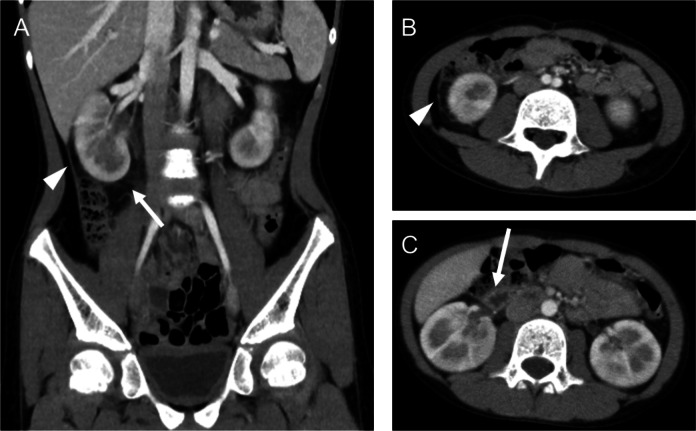

Tosufloxacin, a fluoroquinolone antibiotic, is increasingly prescribed for pediatric patients, particularly for macrolide-resistant Mycoplasma pneumoniae infections in Japan. While its efficacy is well-documented, adverse effects such as renal impairment and gastrointestinal symptoms have raised growing concerns. We report a case of a 10-year-old girl who developed sequential symptoms following tosufloxacin administration. On the day after starting tosufloxacin, she experienced right-sided flank pain, followed by the onset of gastrointestinal symptoms, including abdominal pain, diarrhea, and vomiting, on the subsequent day. Contrast-enhanced computed tomography revealed increased fatty tissue opacity surrounding the kidney and duodenal wall thickening, suggestive of localized inflammation extending from the kidney to adjacent structures. Urine microscopy demonstrated needle- and sea urchin-shaped drug crystals, strongly implicating tosufloxacin in the development of renal and gastrointestinal symptoms. This case provides the first evidence suggesting that kidney inflammation may contribute to gastrointestinal symptom onset via localized inflammatory extension. The patient's symptoms resolved promptly with the discontinuation of tosufloxacin and supportive care. This report underscores the importance of monitoring pediatric patients for renal and gastrointestinal adverse effects following tosufloxacin administration.